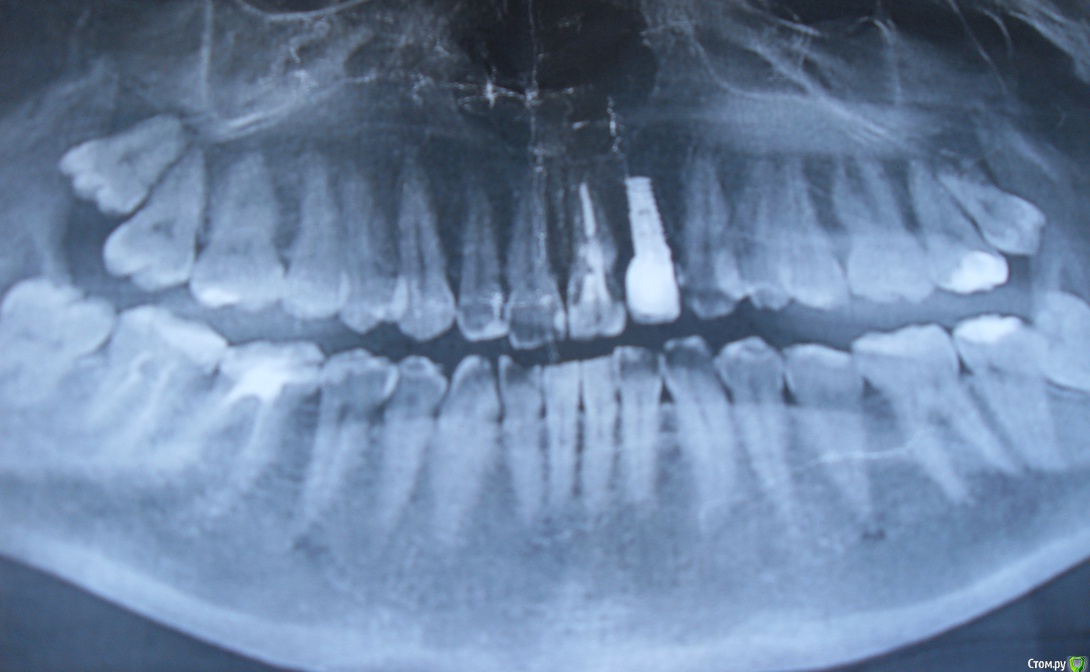

ZeX Опубликовано 10 июля, 2015 Поделиться Опубликовано 10 июля, 2015 Добрый день! Поставил коронку на имплант на постоянный цемент, но она стала шататься через месяц, а также испытываю неприятные ощущения при надавливании на нее. До этого больше 3-х лет ходил со временным цементом и даже забыл, что надо его менять. Подскажите, все ли в порядке с конструкцией самого импланта? Если да, то в чем может быть проблема? Ссылка на комментарий

annda Опубликовано 10 июля, 2015 Поделиться Опубликовано 10 июля, 2015 Возможно,развинитился винт абатмента. 4 Ссылка на комментарий